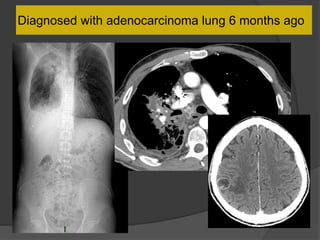

Diagnosed with adenocarcinoma lung 6 months ago

Peritoneal carcinomatosis

Thick enhancing membrane around a

conglomerate of small bowel loops in

the center “cocoon”

Dilated proximal colon

Case 2 Diagnosis: “Cocoon

peritonitis”

•AKA sclerosing

encapsulating peritonitis

•Rare cause of bowel

obstruction due to fibrotic

encapsulation of the bowel

forming a sac or cocoon

•May be idiopathic or

secondary to chronic

peritoneal dialysis, TB,

sarcoidosis, GI malignancy,

fibrogenic foreign material

•Treatment –Surgical

removal of the covering

membrane

Case 13 Diagnosis:Cocoon peritonitis